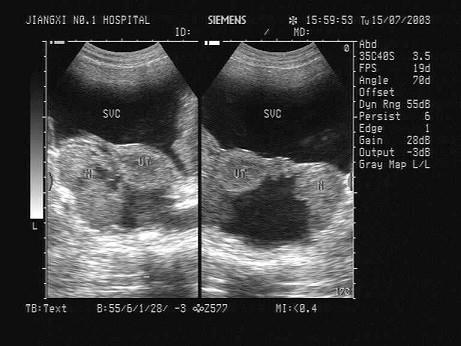

问题 某患者因下腹胀痛就诊,HCG(-),声像图如下,最可能的诊断为?(?)

选项 A.附件炎 B.卵巢癌 C.卵巢囊肿 D.宫外孕 E.盆腔积液

答案 B